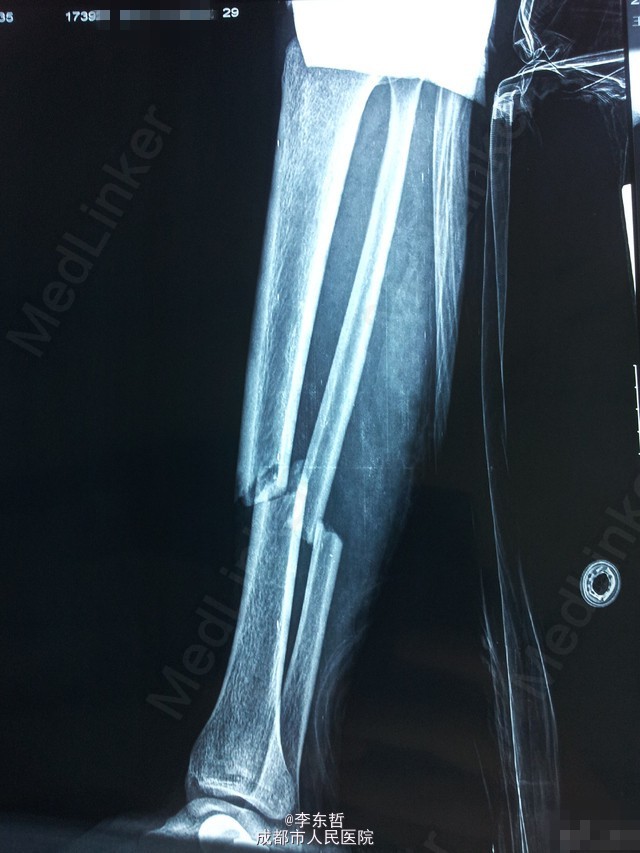

左下肢胫腓骨骨折伴右下肢内外踝骨折一例

患者,女,26岁,外伤致左下肢胫腓骨骨折、右下肢内外踝骨折,入院后右侧临时石膏固定、左侧骨骨牵引10天后,双侧同时手术,左侧胫骨采用MIPPO技术内侧钢板固定。